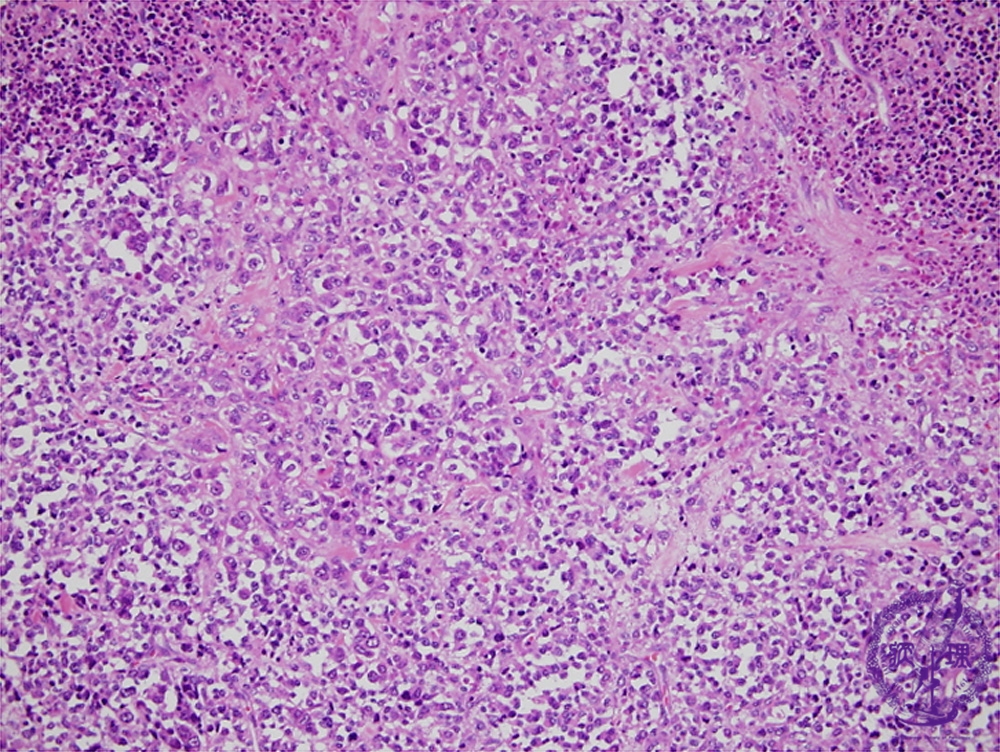

- (6)Rhabdomyosarcoma

Microscopic findings (H.E. low power view): An irregularly-arranged proliferation of round to spindle-shaped small undifferentiated tumor cells admixed with tape- or racket-like or round tumor cells containing abundant eosinophilic cytoplasms. Cytoplasmic cross striations are occasionally identified. Massive intratumoral necrosis frequently detected.